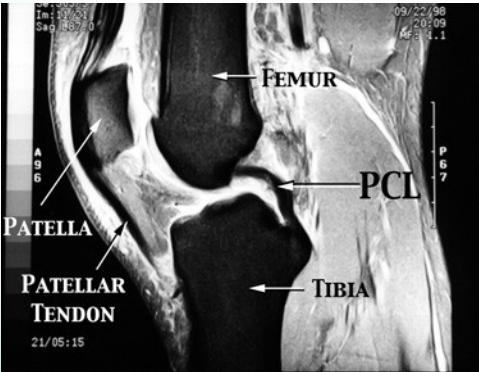

MRI (Gold Standard)

- Best imaging modality for ACL injuries

MRI Findings:

- Normal ACL

- Torn ACL